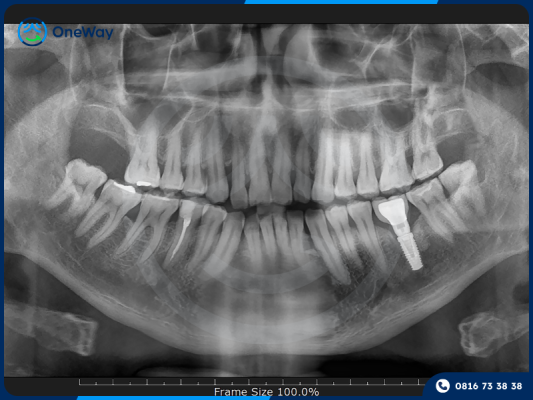

Trồng răng Implant

Cấy ghép Implant là phương pháp phục hình hiện đại, sử dụng một trụ Implant bằng titanium đặt trực tiếp vào xương hàm để thay thế chân răng đã mất. Sau một thời gian, trụ này tích hợp với xương hàm, tạo nền tảng vững chắc để gắn mão răng sứ lên trên, giúp răng hoạt động như răng thật.